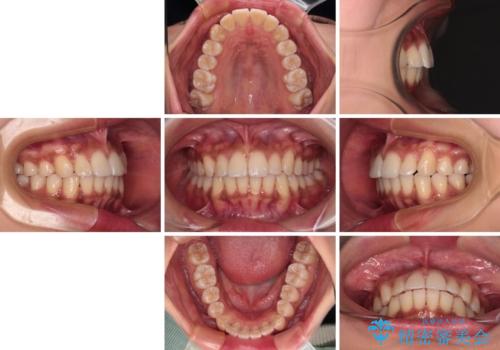

- 全体的な歯列の叢生を気にして来院された患者様です。

奥歯の咬み合わせを見ると、片方は上顎が下顎に対して相対的に前方にある状態でした。

咬み合わせを改善するためには、上顎臼歯を後方に移動させた咬み合わせにする必要があります。

インビザライン単体で改善することも可能ですが、ディープバイトのためインビザライン単体で達成する可能性が低いと考えられたため、カリエール・ディスタライザーという補助装置を併用して、より確実性を上げることとしました。

奥歯の咬み合わせ改善後に、インビザラインにて歯列を整えることとしました。